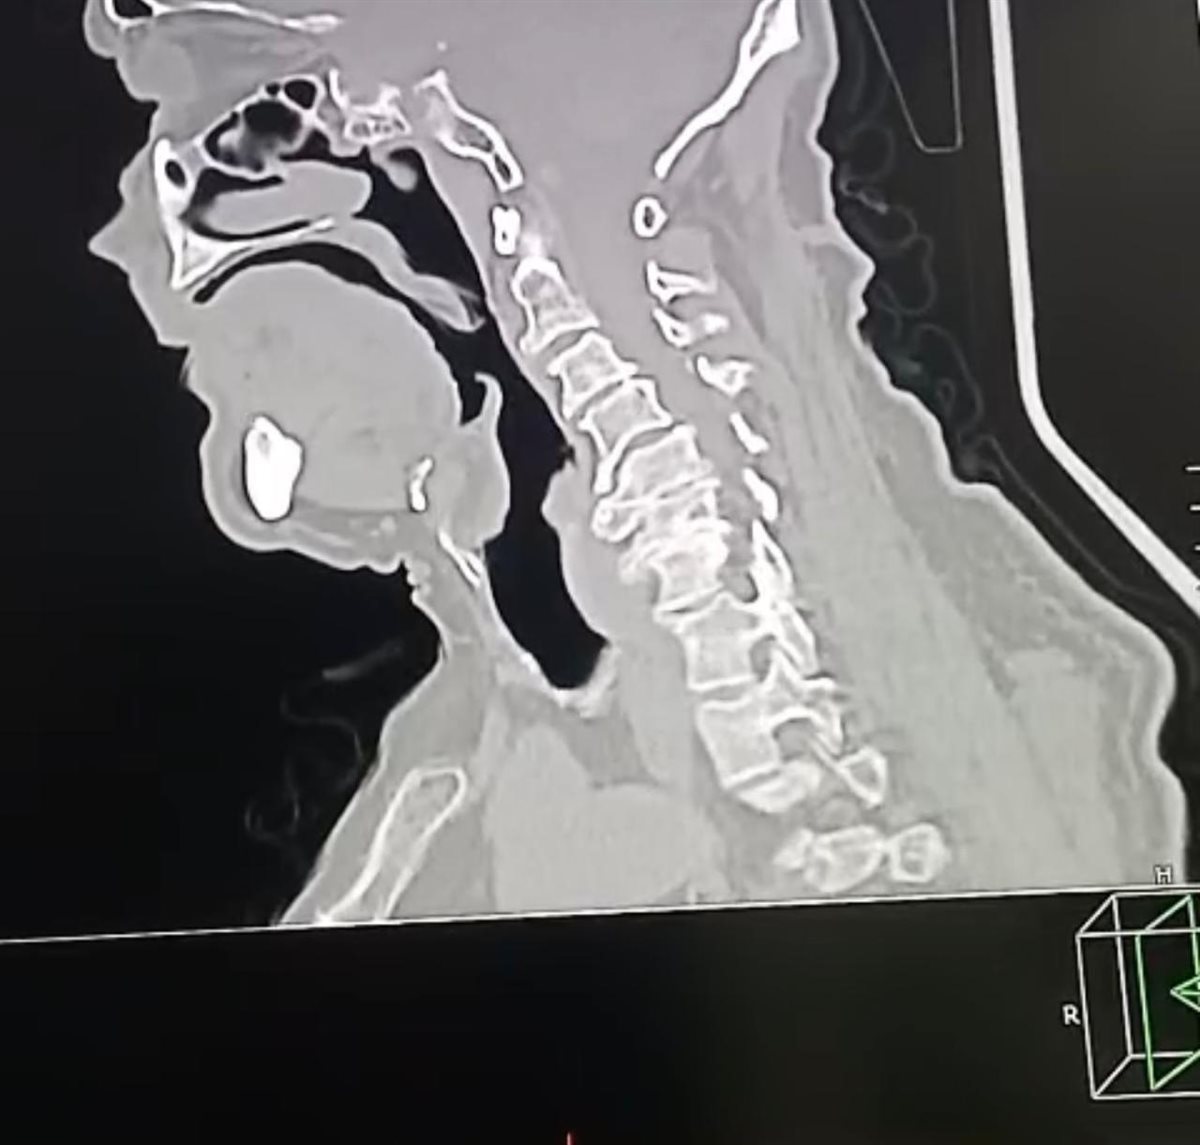

وبإجراء الفحوصات الطبية والأشعات اللازمة، تبين إصابة المريض بانزلاق غضروفي عنقي متعدد على أربعة مستويات، ما أدى إلى حدوث كدمة بالحبل الشوكي وضيق كامل بالقناة الشوكية العنقية، وهي من الحالات شديدة الخطورة التي تستدعي تدخلاً جراحيًا دقيقًا وعاجلًا.

وعلى الفور تم تجهيز الحالة طبيًا من خلال إجراء جميع الفحوصات والتحاليل اللازمة، قبل أن يخضع المريض لجراحة ميكروسكوبية دقيقة ومعقدة، تم خلالها استئصال الغضاريف المنزلقـة، وتركيب أقفاص عنقية مثبتة بدعامات ذاتية (Stand-alone) على أربعة مستويات، وذلك باحترافية عالية، مع خروج المريض من غرفة العمليات في حالة مستقرة وآمنة.